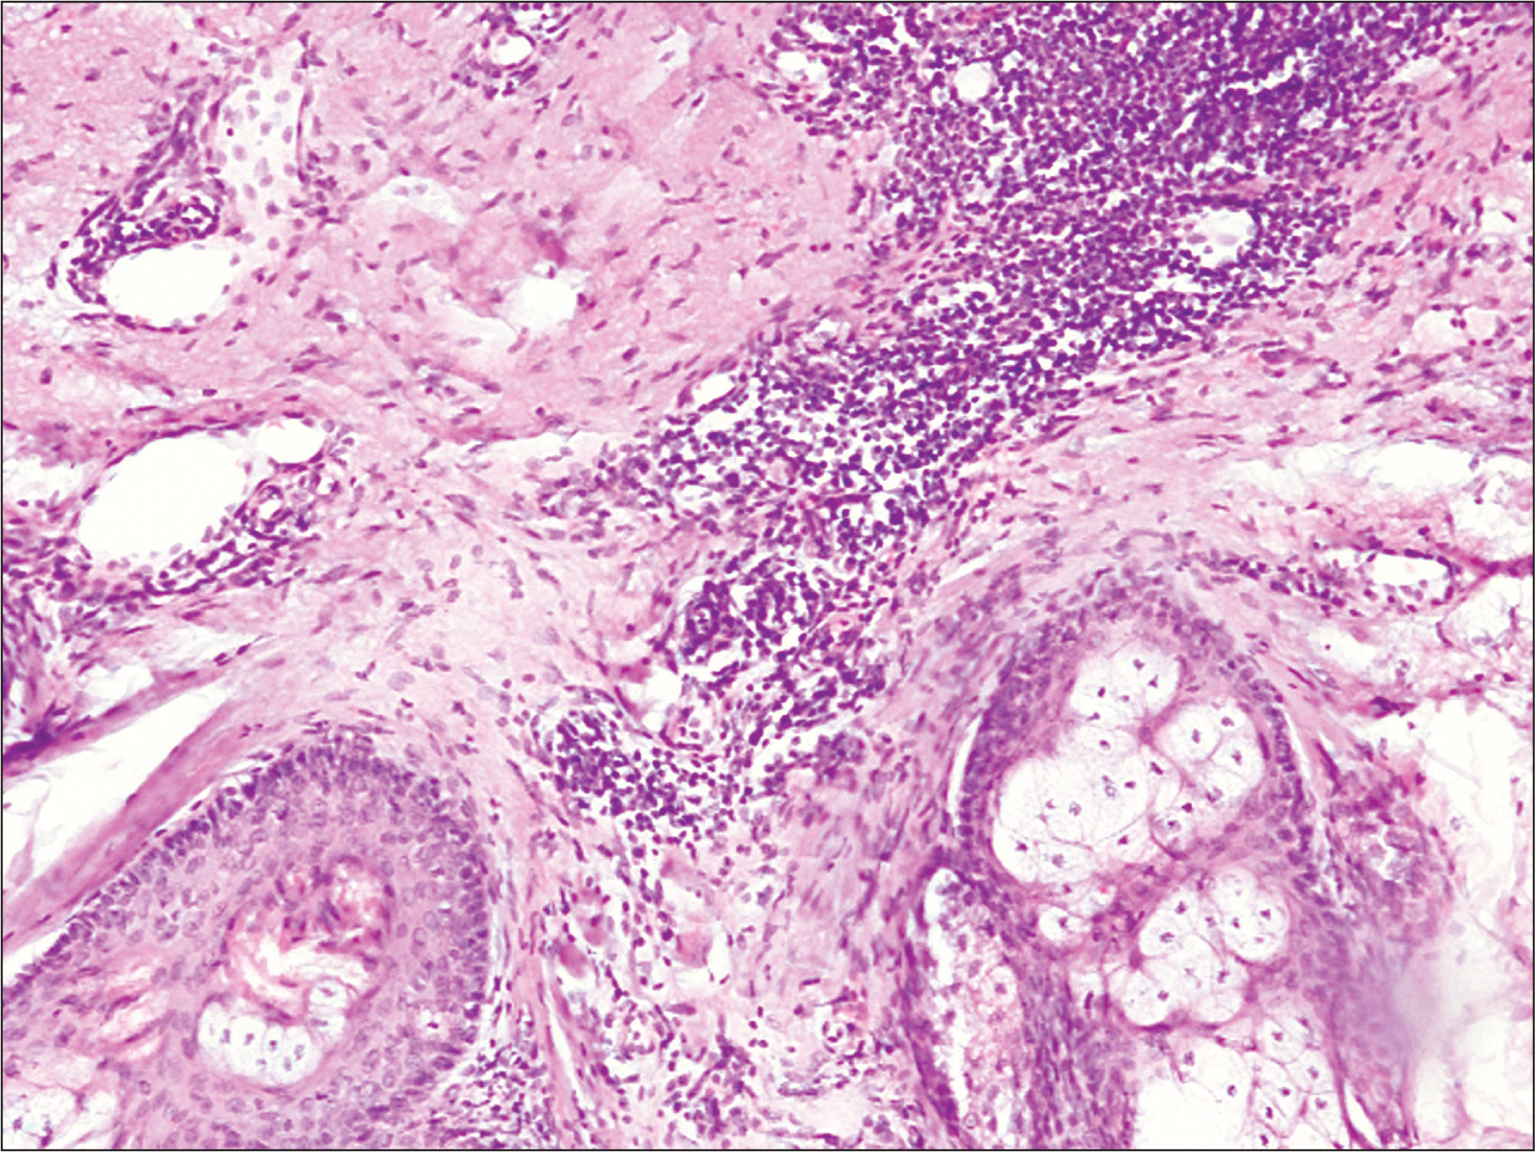

При ультразвуковом исследовании: трансректально – явления хронического простатита; лимфатические паховые узлы не увеличены. Гистологическое исследование: неравномерный акантоз, участки гипер- и паракератоза; многоядерные атипичные клетки с вакуолизированной цитоплазмой, гиперхромированными ядрами, с признаками митозов. В дерме обнаружено расширение сосудов, лимфоцитарные инфильтраты с плазматическими клетками (рис. 3).

Рис. 3. Тот же больной. Гистологическая картина биоптата кожи с края поражения. Наблюдаются неравномерный акантоз, гипер- и паракератоз, многоядерные атипичные клетки с митозами; в дерме – периваскулярные инфильтраты с плазматическими клетками, сосуды расширены.

Заключение: морфологическая картина соответствует эритроплазии Кейра (carcinoma in situ).